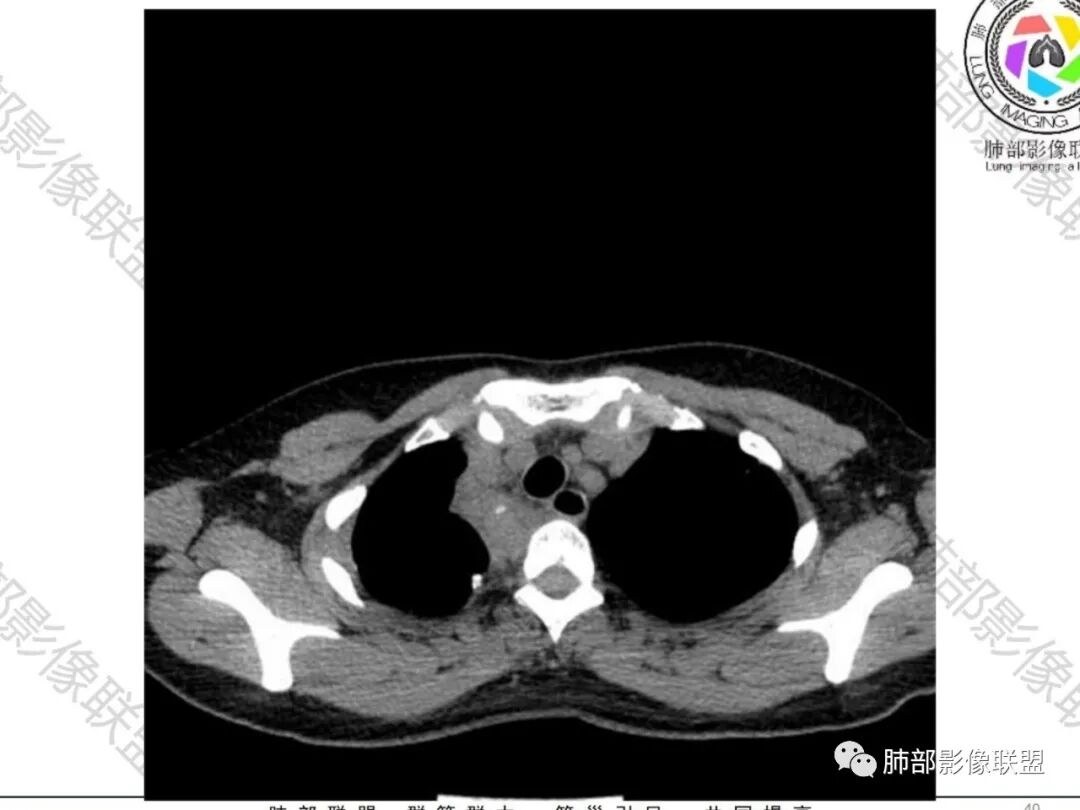

一切∮随缘:双侧胸廓塌陷,以右侧为主,右侧肋间隙狭窄,双肺上叶及右肺下叶胸膜下多发不规则肿块,密度不均匀,内部可见条片状,不规则钙化影,部分钙化不密实,双肺多发纤维索条影,似陈旧性病灶,双侧胸水,临床年轻女性,无感染症状,考虑考虑结核淀粉样变,转移性钙化,弥漫性肺骨化病。

王秀仙:双肺多发条索状及结节状病灶,部分钙化,边界清晰,双侧纵膈胸膜及双侧胸膜可见结块状及弧形软组织肿块,内见多发钙化灶,右侧胸腔塌陷,考虑结核伴淀粉样变性。鉴别胸膜间皮瘤。

丽:双肺散在索条及条片状高密度影,边界清晰,部分实变内可见钙化,支气管管壁增厚,双肺胸膜局限性增厚伴钙化,部分肋骨密度增高,首先考虑结核并淀粉样变性,鉴别转移性钙化,肿瘤样钙质沉着症,胸膜间皮瘤。

尘缘:青年女性,痰中带血,胸痛2月,无发热盗汗,实验室检查,有贫血,总蛋白降低,血沉情况未知,肿标基本正常。影像表现:双上肺小叶间隔增厚,双侧胸膜广泛不规则增厚,胸膜下多发肿块伴不规则钙化,右侧肋骨破坏。纵隔淋巴结肿大不明显,双肺门淋巴结肿大,部分融合,分析思路:一、感染性病变,1、结核,青年女性,胸膜增厚,多发肿块伴钙化,有咳嗽胸痛,痰中带血,要考虑,但无结核中毒症状,病史仅两月却钙化太明显,肺内没有明显树芽征,存疑,2、其他感染,无炎性指标支持,白细胞不高,可能性小。二、非感染性病变,1、尘肺,胸膜增厚,钙化,胸膜下钙化性肿块,要考虑,但肺内无粉尘结节,无职业史,可能小。2、转移性钙化,无肾脏病史,无血清钙磷代谢异常指标支持,肺内间质无钙沉积改变,基本排除。三、肿瘤性病变,1、肺癌伴转移,双上肺有小叶间隔增厚,双肺门有淋巴结肿大,要考虑,但青年女性,病史两月,钙化太多太广泛,肿标基本正常,可能性小。2、骨肉瘤转移。15-30岁青年人,是骨肉瘤高发年龄,肺内多发成骨样钙化转移灶,双上肺小叶间隔增厚符合癌淋样表现,右侧肋骨破坏,要高度怀疑,需要详细询问病史及手术史。3、软骨来源肿瘤伴肺内转移,右侧肋骨虽有破坏,但无明显软骨样破坏及钙化。可能小。4、其他肿瘤伴转移,青年女性,其他恶性肿瘤能广泛发生钙化性转移的可能性小。综上所述:骨肉瘤伴右侧肋骨及胸膜转移,胸膜下转移,肺内癌淋可能最大,结核不完全除外,下一步需要,仔细询问病史,如果有骨肉瘤史,则基本确诊,如果没有,需要进一步问询呼吸系统症状,病程,以前的影像对照,了解肾脏情况,查血清钙磷指标。

南边:33岁,女性

咳嗽/胸痛2月,偶有痰中带血

右肺体积缩小,上叶见空洞影

上叶内多个结块,边缘有膨隆,内有钙化灶

钙化灶密度较高,环形/结节状

胸膜及附近肺内见多发结节/斑块